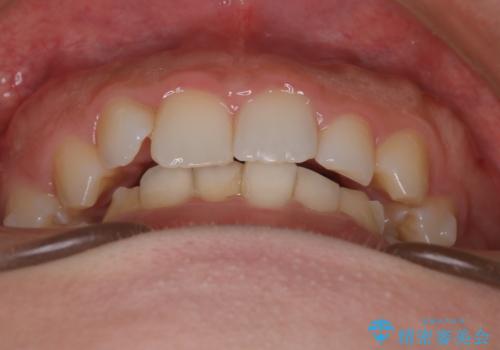

インビザラインで整える深い噛み合わせ

- 患者様は、ディープバイト(深い噛み合わせ)と、咬合平面の左下がりが気になるとのことでご来院されました。診断の結果、非抜歯で治療可能と判断し、透明なマウスピース型矯正装置「インビザライン」を用いる方針としました。治療では、歯列全体の調整を行いながら、咬合平面の水平化を重点的に進める計画を立案しました。2年間で計画的にマウスピースを交換し、左右のバランスと噛み合わせの改善を目指しました。

ディープバイトの矯正は、噛み合わせが深くなりがちなため、細心の注意を払いながら進める必要があります。本症例では、奥歯の高さを調整しつつ前歯の噛み合わせを浅くすることで、全体の咬合バランスを整えました。また、咬合平面の左下がりを修正する過程で、歯列に不均等な力がかからないよう、インビザラインのアタッチメント配置を最適化しました。患者様には装着時間を守っていただき、治療が計画通り進むよう協力をお願いしました。治療終了後には、リテーナーを装着して安定性を確保しました。